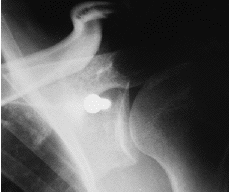

Ninguno de los pacientes intervenidos presentó nuevas luxaciones después de la cirugía. El déficit medio de rotación externa comparando las dos extremidades fue de 9° (* = 6°) y no hubo diferencias significativas en cuanto a rotación interna y la antepulsión. Un 60% de las pastillas estaban en el tercio inferior, el 20% en el tercio medio y otro 20% en el superior (Fig. 1). El 39% estaban enrasadas con el margen anterior de la glena, el 22% se habían colocado externas (Fig. 2) y el 39% se encontraban en situación demasiado medial (Fig. 3). En tan solo uno de los casos se utilizaron dos tornillos para fijar la pastilla ósea. En el resto se utilizó un tornillo pero sólo en la mitad de los casos éste atravesaba las dos corticales (Fig. 4). El tipo de tornillo más utilizado fue el maleolar (n = 18), y en tres casos se implantó un tornillo de escafoides. La mitad de las pastillas mostraban signos de consolidación, mientras que en el resto, el 21% habían migrado (Fig. 5) y el 28% se mantenían en posición merced a una unión fibrosa (Fig. 6). En ningún caso se evidenció osteolisis de la pastilla. Tan solo dos pacientes cumplían todos los parámetros radiográficos ideales. Ningún paciente requirió ser reintervenido por complicaciones clínicas posteriores, o por migración o rotura del tornillo. No se detectaron lesiones vasculonerviosas ni infección postoperatoria en ningún paciente.

Figura 1. Proyección antero-posterior. Situación de la pastilla ósea en tercio superior de la glena.